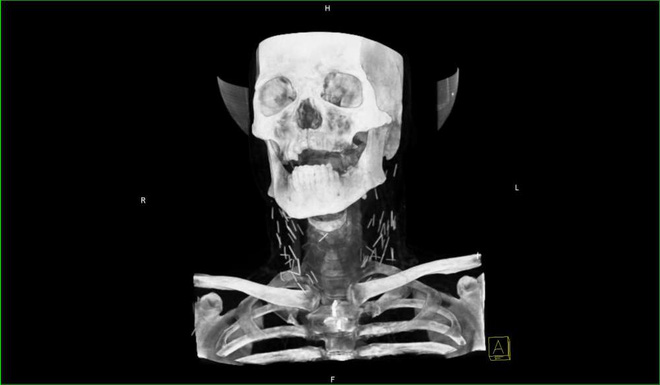

Mới đây một hình X-quang đã được chia sẽ lên mạng. Nhiều người nhìn bức hình đã phải giật mình. Trong cơ thể người nghiện có rất nhiều mũi kim.

Và mới đây, một bức hình chụp X-quang phần cổ của một con nghiện heroin lâu năm đang được chia sẻ với tốc độ chóng mặt. Quan trọng hơn, ai nhìn thấy nó cũng phải rùng mình.

Bạn có quan sát thấy những đường thẳng chi chít ở 2 bên cổ không? Bạn nghĩ đó là gì? Câu trả lời là những mũi kim tiêm.

Theo đó, bệnh nhân là một con nghiện heroin lâu năm, đến bệnh viện trong tình trạng viêm phổi nặng. Nhưng đến khi đưa vào máy chụp X-quang, người ta phát hiện ra hàng tá mũi kim gãy vẫn còn trong cổ anh ta.

Ví dụ như vào năm 2006, trang tin từ công ty y dược UBM Patient Care đã đăng tải trường hợp của một bệnh nhân 53 tuổi, có tiền sử lạm dụng heroin trong 30 năm. Và bên trong cổ của ông có tới 17 mũi kim gãy.

"Kim gãy và lưu lại trong cơ thể khi tiêm ma túy là hiện tượng không hiếm" - một bác sĩ từ công ty cho biết. "Từng có một nghiên cứu cho thấy có thể 20% con nghiện heroin đã trải nghiệm cảm giác kim gãy khi đang tiêm chích".